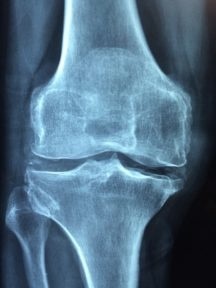

Osteoporosis is a condition where the bones can weaken and become brittle and prone to fractures from even the mildest stresses such as bending or coughing. Older women, especially Caucasian and Asian women, are at a much higher risk of developing osteoporosis. As this condition weakens the bones, fractures related to osteoporosis are common and often occur in the spine, wrist and hip.

Your bones are a dynamic system and are being constantly renewed – old bone is broken down and new bone is made. Osteoporosis occurs when new bone creation is unable to keep up with the loss of previous, old bone. Younger people’s bodies break down and build up new bones much faster, but this process can slow down as people age.